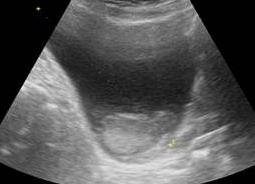

Здоровый мочевой пузырь на экране должен быть представлен в черном цвете. В середине он полый, и в нем не должно обнаруживаться ничего «лишнего», в частности, камней и песка.

• Форма органа округлая, симметричная, имеющая четкие ровные контуры. В случае изменения этих показателей возникают подозрения на наличие инородных тел, образование полипов и присутствие травм.

• Толщина стенки не должна превышать 2 мм. В случае цистита на УЗИ отмечается утолщение. При этом такое явление может сопровождать не только эту патологию, но и указывать на наличие новообразования.

• Рассмотрим объем – емкость в норме составляет для мужчин от 350 до 750 мл, для представительниц слабого пола от 250 до 550 мл.

• В нормальном состоянии полость органа не содержит осадок, хлопья либо конкременты. Если диагностируются камни, ультразвук позволяет определить их размеры.

Расшифровка УЗИ мочевого пузыря должна производиться только урологом, ведь простого сравнения полученных данных в протоколе обследования со средней нормой недостаточно. Специалист учитывает особенности организма каждого конкретного пациента, симптоматику, с которой он обратился, и другие факторы. В норме орган должен быть:

• круглым на поперечной и яйцевидным на продольной сканограмме;

• эхонегативным по структуре;

• с соразмерными четкими и ровными краями;

• чистым внутри, то есть в органе не должно быть никакого налета или осадка;

• со стенками толщиной в 3-5 мм.